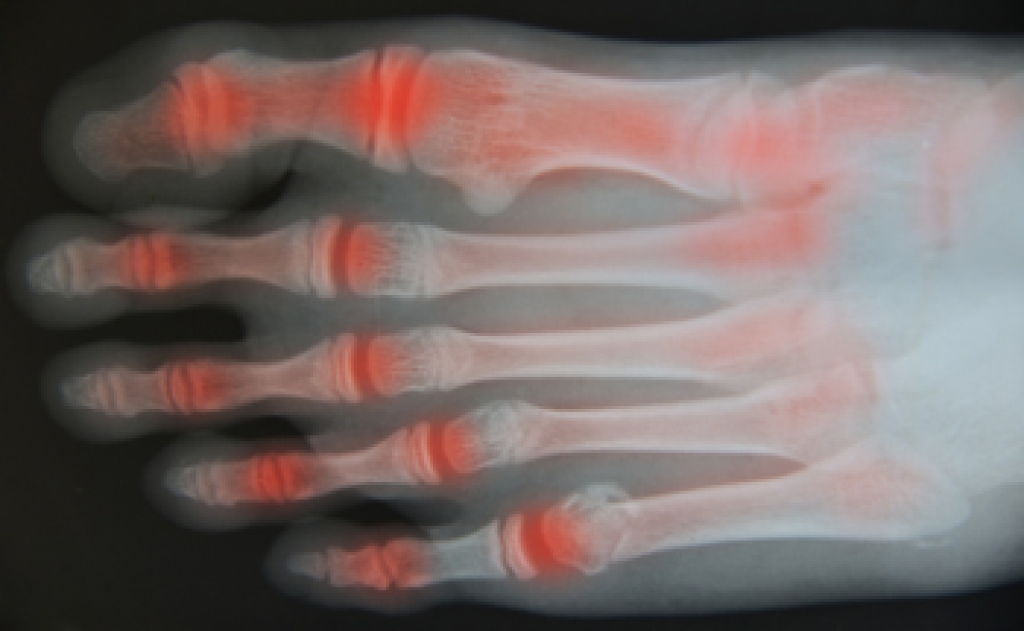

Dealing With Osteoarthritis

Osteoarthritis is a disease that often targets people as they get older. What happens is that the cartilage between the joints wears down, removing the cushion between the bones and causing them to touch. This brings intense pain and can cause damage to the bones. In some cases of osteoarthritis, bumps known as Herberen’s and Bouchard nodes form at the joints, particularly in the fingers and toes. There is no cure for osteoarthritis, which is also a progressive disease, and the cause is unknown. In some cases, it is brought on by other conditions, including nervous system disorders, a buildup of certain minerals in the body, congenital diseases, and bone disorders. Treatment is available for osteoarthritis ranging from non-steroidal anti-inflammatory medication and topical creams that help reduce pain to surgery that replaces the cartilage or the joint itself. If you believe you have osteoarthritis that is affecting your feet and ankles, please see a podiatrist for treatment options.

Arthritis can be a difficult condition to live with. If you are seeking treatment, contact Jeffrey Radack, DPM from Texas Regional Foot & Ankle Clinics. Our doctor can provide the care you need to keep you pain-free and on your feet.

Arthritic Foot Care

Arthritis is a joint disorder that involves the inflammation of different joints in your body, such as those in your feet. Arthritis is often caused by a degenerative joint disease and causes mild to severe pain in all affected areas. In addition to this, swelling and stiffness in the affected joints can also be a common symptom of arthritis.

In many cases, wearing ill-fitting shoes can worsen the effects and pain of arthritis. Wearing shoes that have a lower heel and extra room can help your feet feel more comfortable. In cases of rheumatoid arthritis, the arch in your foot may become problematic. Buying shoes with proper arch support that contour to your feet can help immensely.

Alleviating Arthritic Pain

- Exercises that stretch the foot can prevent further pain and injury and increase mobility

- Most of the pain can be alleviated with anti-inflammatory drugs, heat, and topical medications

- Massages can help temporarily alleviate pain.

It is best to see your doctor for the treatment that is right for your needs and symptoms. Conditions vary, and a podiatrist can help you determine the right method of care for your feet.